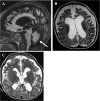

Case presentation: Here, we describe a six-year-old boy with developmental delay, hypotonia, and failure to thrive who developed an early-onset DEE consistent with Lennox-Gastaut Syndrome (LGS), which has not previously been observed in this disorder. He had dysmorphic features including bilateral macrotia, overriding second toes, a depressed nasal bridge, retrognathia, and downslanting palpebral fissures, and he did not demonstrate progressive microcephaly. Whole genome sequencing identified two variants in RARS2, c.36 + 1G > T, a previously unpublished variant that is predicted to affect splicing and is, therefore, likely pathogenic and c.419 T > G (p.Phe140Cys), a known pathogenic variant. He exhibited significant, progressive generalized brain atrophy and ex vacuo dilation of the supratentorial ventricular system on brain MRI and did not demonstrate PCH. Treatment with a ketogenic diet (KD) reduced seizure frequency and enabled him to make developmental progress. Plasma untargeted metabolomics analysis showed increased levels of lysophospholipid and sphingomyelin-related metabolites.